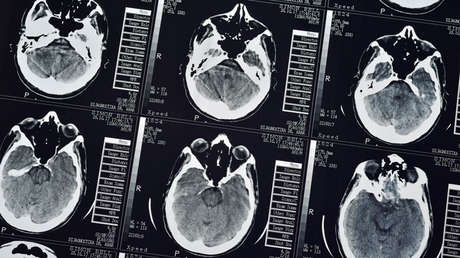

La investigación, publicada en la revista Brain Imaging and Behavior, evaluó los resultados de las resonancias magnéticas de tres grupos de personas, que participaron de manera voluntaria: 203 homicidas, 475 violentos pero no homicidas y 130 mínimamente violentos. Quedaron excluidos los cómplices de asesinato y aquellos involucrados en casos de posible muerte accidental.

El resultado fue que los asesinos presentaban una significativa reducción en la materia gris respecto del resto de los delincuentes, entre los que hubo pocas diferencias.

En ese sentido, el neurocientífico Kent Kiehl explicó que las mayores diferencias se presentaban en la corteza frontal orbital y los lóbulos temporales anteriores, a la vez que detalló que "los hombres que cometieron homicidio tenían menos materia gris en estas regiones que otros delincuentes violentos o no violentos".